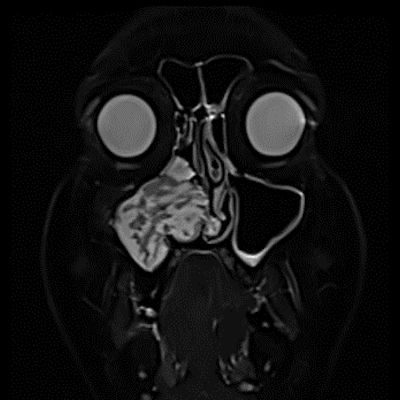

- A) Koronal T2 ağırlıklı görüntülerde sol maksiller sinüs lümenini dolduran, belirgin ‘convoluted’ (karmaşık-kıvrımlı) serebriform patern sergileyen lezyon (oklar), kontrastlı seride heterojen ve yoğun kontrastlanma göstermektedir (oklar). Perfüzyon incelemesinde pedinkülünde perfüzyon artışı gösterdiği, diğer kontrastlanan segmentlerin nispeten hipoperfüze olduğu görülmektedir (ok).

- Inverted papilloma (Schneiderian inverted papilloma), sinonazal mukozanın benign ancak lokal agresif, nüks potansiyeli yüksek ve malign transformasyon (özellikle skuamöz hücreli karsinom) ile ilişkilendirilebilen epitelyal bir tümörüdür. Histopatolojik olarak, respiratuar epitelin stromaya doğru endofitik invajinasyonu ile karakterizedir. En sık lateral nazal duvar ve maksiller sinüs kaynaklı olup, tek taraflı nazal obstrüksiyon ve sinüzite benzer klinik presentation ile karşımıza çıkar

- En sık lateral nazal duvar ve maksiller sinüs orijinlidir.

- MR incelemesinde sinonazal inverted papilloma tipik olarak T2 ve post-kontrast T1 serilerde ‘convoluted’ serebriform paternde heterojen sinyal ve kontrastlanma gösteren, pedinküler orijininde daha belirgin perfüzyon artışı sergileyen, genellikle difüzyon kısıtlaması izlenmeyen ve komşu sinüs duvarlarında ekspansiyona bağlı remodelinge yol açabilen benign ancak lokal agresif karakterde bir yumuşak doku kitlesi olarak izlenir.